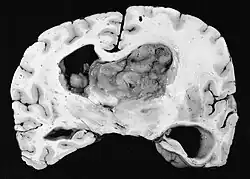

Subependymale Riesenzellastrozytome treten insbesondere bei Kindern und jungen Erwachsenen auf. Da der Tumor bevorzugt in der Wand des Ventrikelsystems in der Nachbarschaft der Foramina Monroi entsteht, ist mit zunehmendem Wachstum häufig der Liquorabfluss gestört. Der Tumor wächst in der Regel sehr langsam und zeigt sich in der Bildgebung als umschriebene Raumforderung mit Verkalkungen und Zeichen älterer Blutung. In manchen Fällen ist das SEGA die Erstmanifestation einer tuberösen Sklerose (TSC) und zählt daher zu einem diagnostischen Hauptkriterium. Allerdings entwickeln nur 6–16 % aller TSC-Patienten ein SEGA.

Neuropathologie

Histologisch sind für den Tumor astrozytäre Riesenzellen charakteristisch; die Morphologie der Tumorzellen kann jedoch von polygonalen Zellen mit glasigem Zytoplasma und ganglioiden Kernen bis hin zu spindelförmigen Zellen in einer fibrillären Matrix reichen. Die Tumorzellen zeigen eine variable Expression von GFAP, S-100, Synaptophysin und Neurofilament.